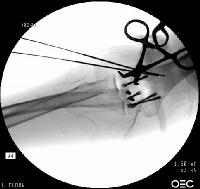

Open reduction via olecranon osteotomy.  The ulnar nerve is  retracted with a penrose drain. The articular surface was reconstructed, then secured to the shaft. After recovering the rotated anterior articular fragment, the anterior and posterior halves of the central articular component were secured with .062" pins. These pins were replaced one at a time with Herbert screws.

Click for larger image

In similar steps, the reconstructed central articular component was secured to the proximal humerus with pins. Once satisfactory reduction was obtained (not yet, as seen here...), the pins were replaced by more Herbert screws. This allowed fixation of the purely osteochondral segments without prominent harware.